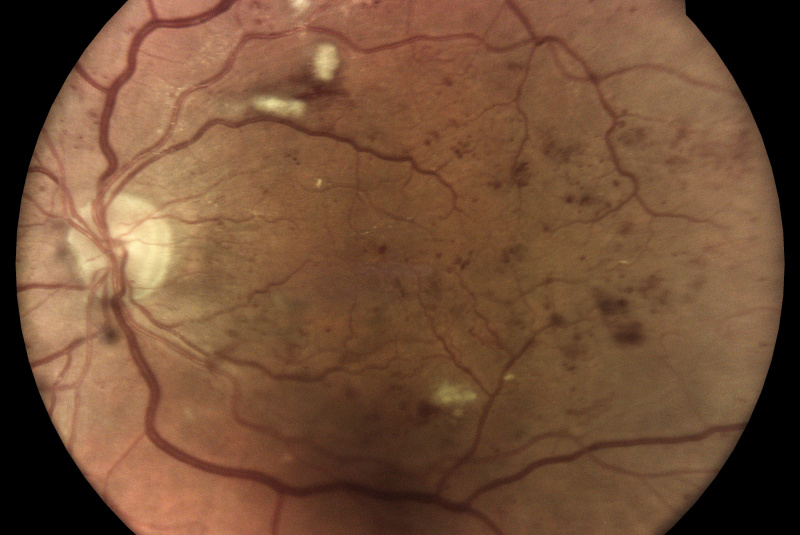

Oproti běžným fundus kamerám je tu využitá patentovaná technológia iCare DRS Plus Confocal Technology. Znížená intenzita záblesku má šetrnejší účinok na zrenicu. Prostredníctvom tohto nemydriatického zariadenia je možnosť vidieť jemné štruktúry sietnice a cievneho systému aj skrz velikost zrenice od 2,5 mm.

Fundus kamera iCare DRSplus urobí celkovo 4 vysoko kvalitné snímky (dve z pravého a dve z ľavého oka), ktoré sa automaticky ukladajú na cloud a posielajú sa na spracovanie AI - umelej inteligencii. Report je dostupný ihneď a ten je možné prekonzultovať s pacientom počas tej istej návštevy u lekára.

- infračervené mapy zvýrazňujúce svetlé a červené lézie/poškodenia

Diabetická retinopatia

Diabetická retinopatia je hlavnou príčinou straty zraku u dospelých vo veku medzi 20 - 74 rokov. Viac ako jedna tretina z odhadovaných 285 mil. ľudí s cukrovkou na celom svete vykazuje príznaky diabetickej retinopatie. Diabetická retinopatia je na vzostupe v dôsledku zvyšujúcej sa prevalancie cukrovky, stárnutia populácie a predlžujúcej sa dĺžky života ľudí s cukrovkou.